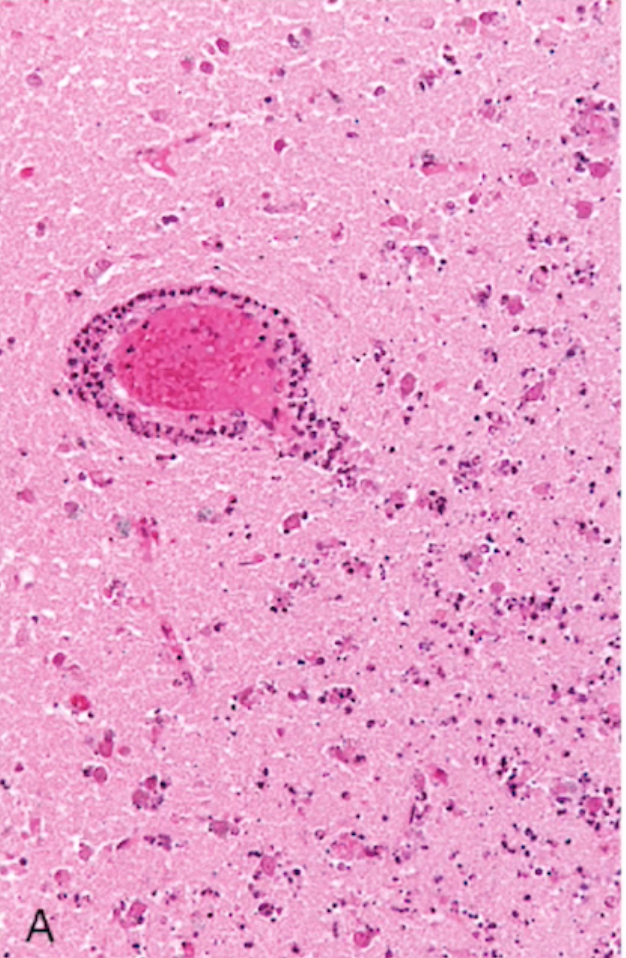

Focal Cerebral Ischemia